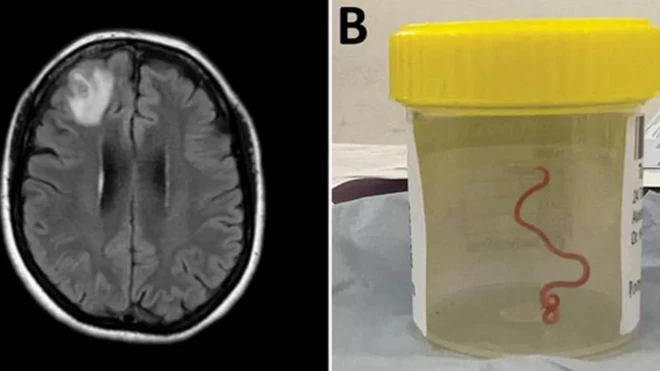

사진 출처, UNIVERSITY OF MICHIGAN